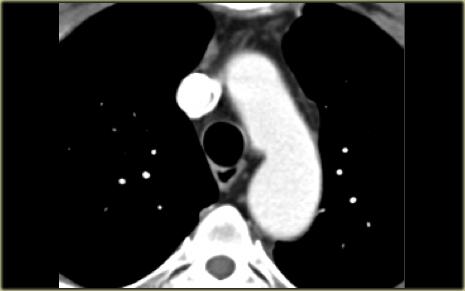

Describe the images on the left and then continue reading.

On the left side there is a vascular structure, that runs inferiorly below the level of the left hilum and enters into a dilated coronary sinus.

The diagnosis is left or double superior vena cava.